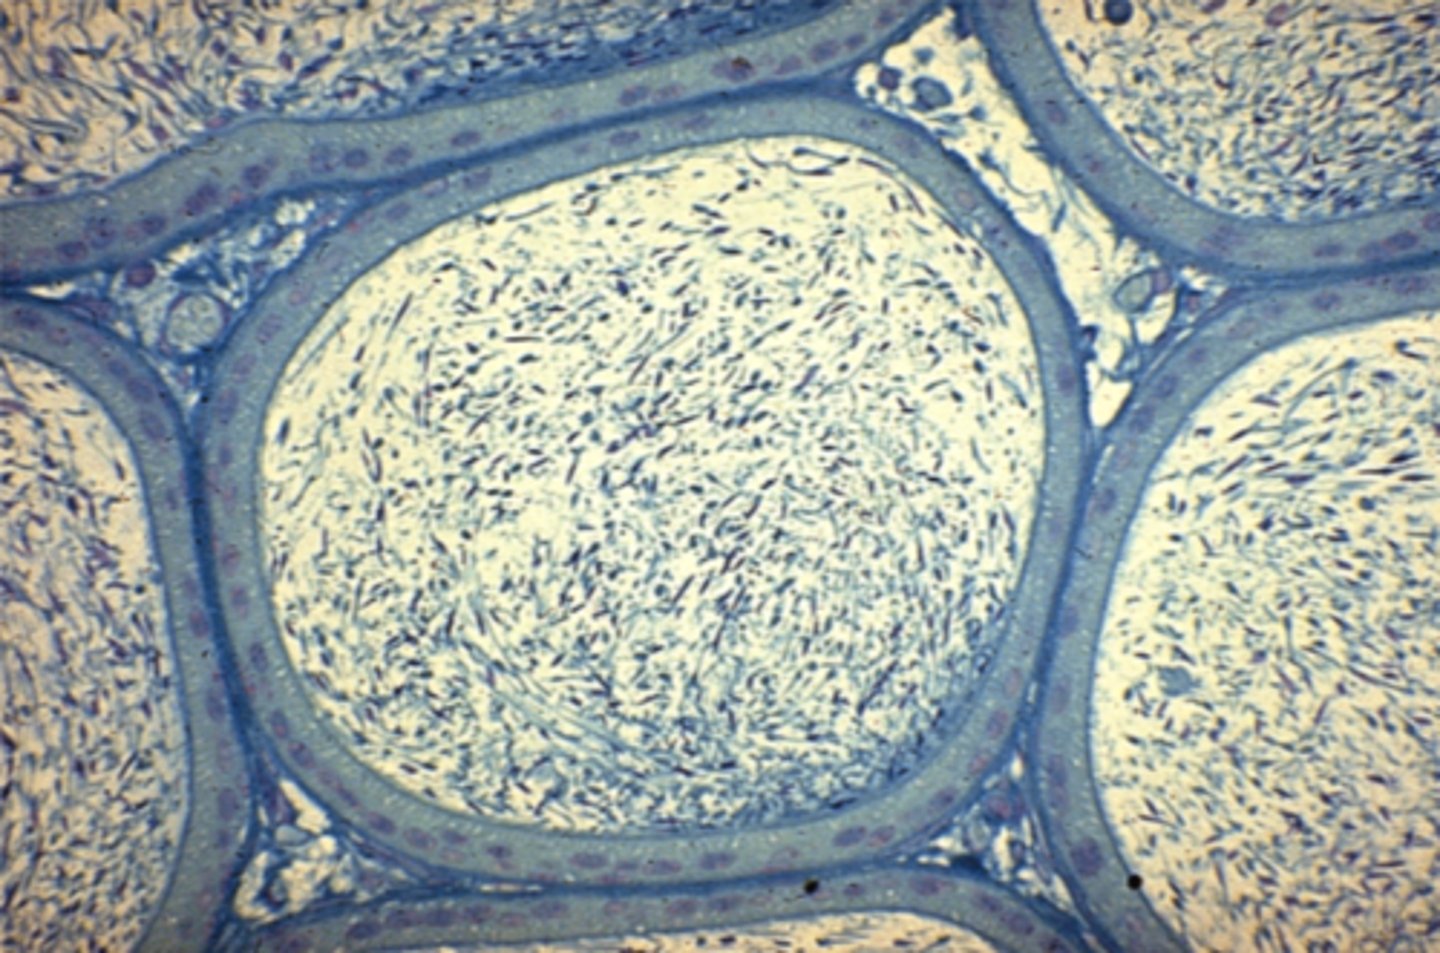

Vas deferens

What is this?